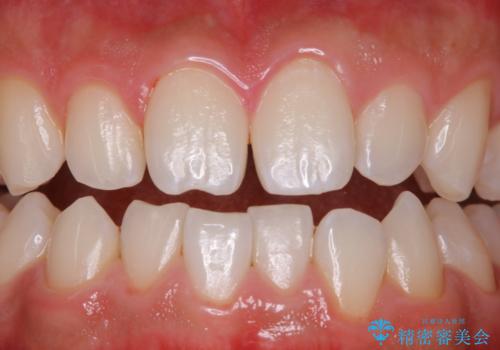

PMTC(歯科衛生士による専門的クリーニング)にはコースがあります。

前歯をメインに行う30分5000円+taxと全体的に行う60分10000+taxコースです。お口の状態や、ご希望により、担当衛生士と相談をしてからの施術となります。

今回は、前歯メイン希望とのことでしたが、歯石やプラークが薄い付着だったため、30分コースの中で全体的クリーニングが行えました。

状態次第では、60コースでも全ての汚れが取り切れない場合もあります。